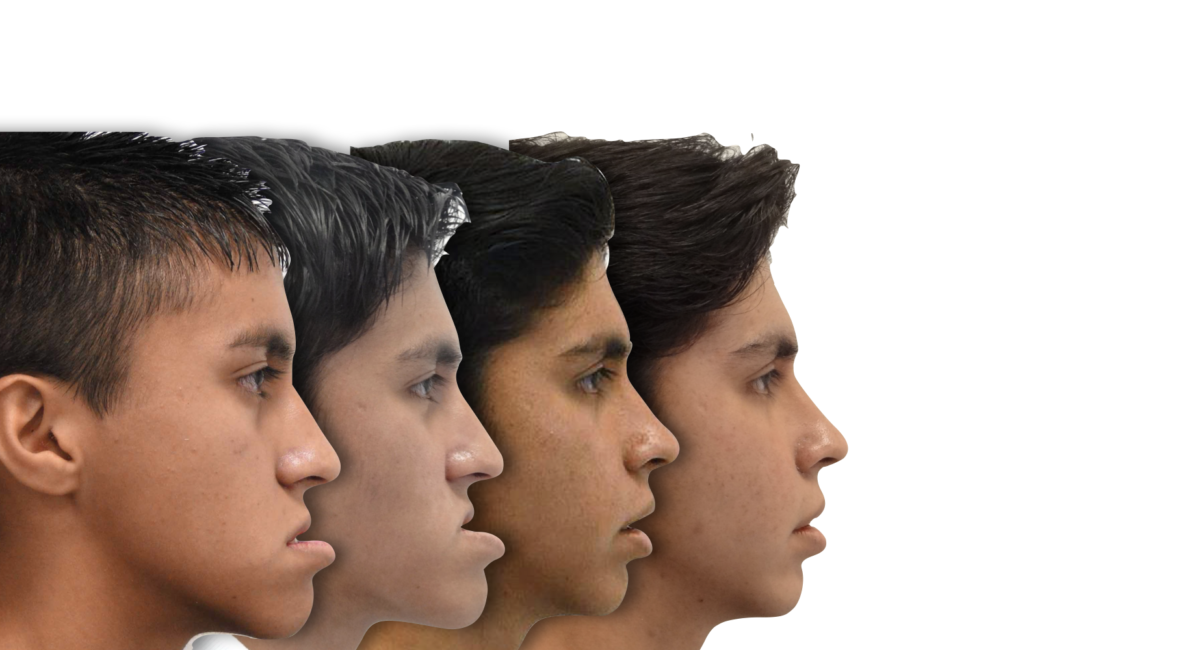

El siguiente caso clínico se trata de un paciente masculino de 18 años (al concluir su

tratamiento). Es un caso Orto/Quirúrgico complejo, donde el paciente presentaba una clase

ósea III debido a una hipoplasia maxilar y un aumento en la longitud del cuerpo mandibular,

ademas de presentar un biotipo dolicofacial (crecimiento de la cara hacia abajo). Este caso fue uno de los primeros casos quirúrgicos en concluir el Dr Quijada cuando aun era residente de la especialidad hospitalaria, donde hubo un trabajo en conjunto.

La primer fase que fue una expansión palatina y tracción de múltiples piezas incluidas en maxilar fue realizada por la Dra Scarlett Escobar, y posteriormente fue heredado el caso al Dr Francisco Quijada para su planeación y tratamiento Ortodóncico/Quirúrgico, una vez concluido la fase de Ortodoncia, estaba listo para la fase Quirúrgica, trabajando en conjunto con el servicio de Cirugía Maxilofacial, una vez concluida la cirugía el paciente estuvo listo para concluir su tratamiento y gozar de una fantástica mejoría en la estética facial, dental y una correcta función oral.

Paciente masculino con prognatismo mandibular severo y discrepancia esquelética Clase III. Presentaba mordida cruzada anterior, dificultad para masticar y alteración estética marcada. Se realizó tratamiento orto-quirúrgico con preparación ortodóncica y cirugía bimaxilar. El resultado final fue una oclusión funcional estable y una armonía facial significativa.

- Diagnóstico : Clase ósea III por hipoplasia maxilar

- Año : 2012